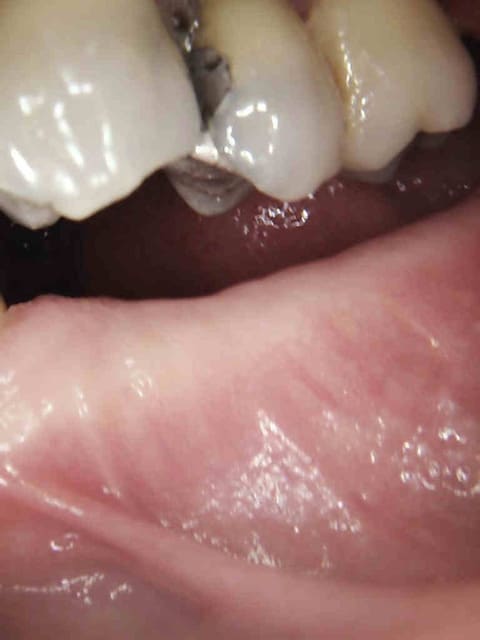

Voir cas ci dessous.

1 t0vddl - Eugenol

2 oailks - Eugenol

De toutes façons, au vu de la gueule de ses incisives, ce sera vite un complet si l'étiologie n'est pas maîtrisée.

Ca c'est rien j'ai le meme en inversé d'articulé. -))))